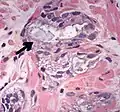

Intraductal carcinoma of the prostate with an infiltrative growth pattern may be morphologically difficult to distinguish from invasive cancer. One focus shows comedonecrosis (arrow), morphologically suggesting Gleason pattern 5 invasive carcinoma (a haematoxylin and eosin, b CK5/6)[19]

Intraductal carcinoma of the prostate with very patchy basal cells identified by immunohistochemistry. At least some of the glands lacking basal cell immunoreactivity represent intraductal rather than invasive carcinoma (a haematoxylin and eosin, b CK 5/6)[19]